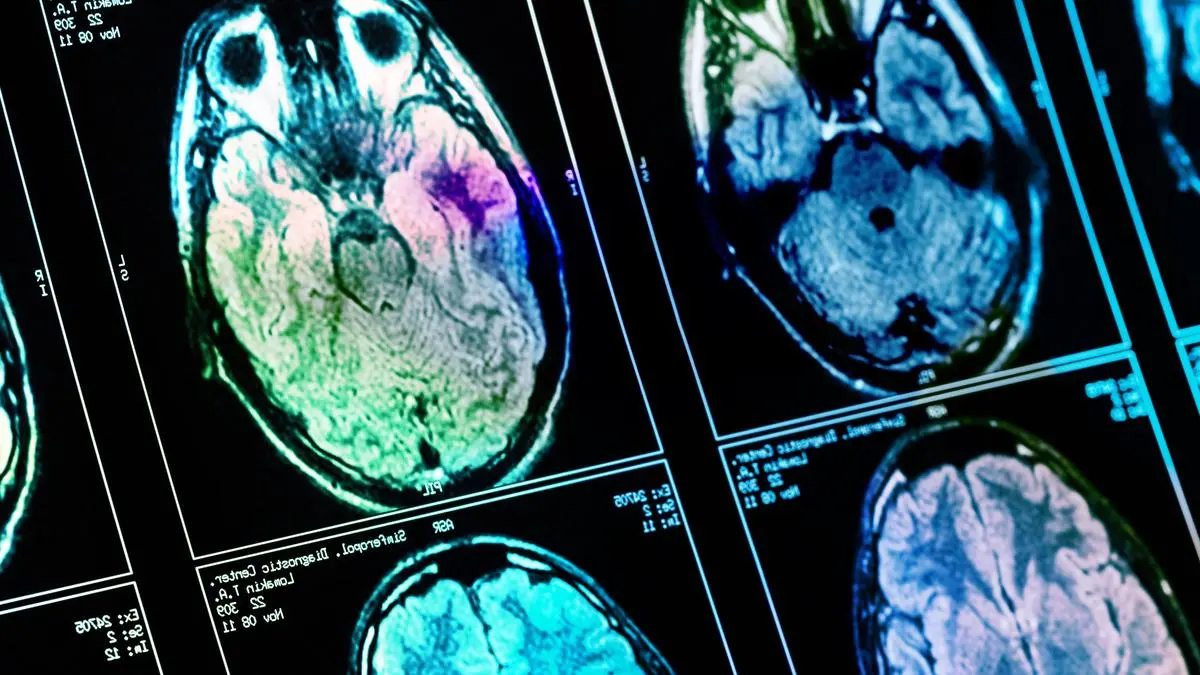

Veränderungen an Hirnstruktur

Wie Covid-19 das Gehirn schädigt

Wie bei so vielen gesundheitlichen Folgen von Covid-19 ist auch hier die überschießende Reaktion des Immunsystems die Ursache. Diese kann die Blut-Hirn-Schranke beeinträchtigen.